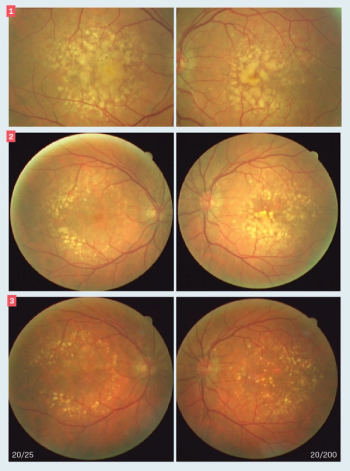

This case illustrates stability of an extrafoveal lesion without vision loss.

Case report details diagnosis based on imaging diagnostics.

Appropriate identification and management of pigmented fundus lesions can be made clinically